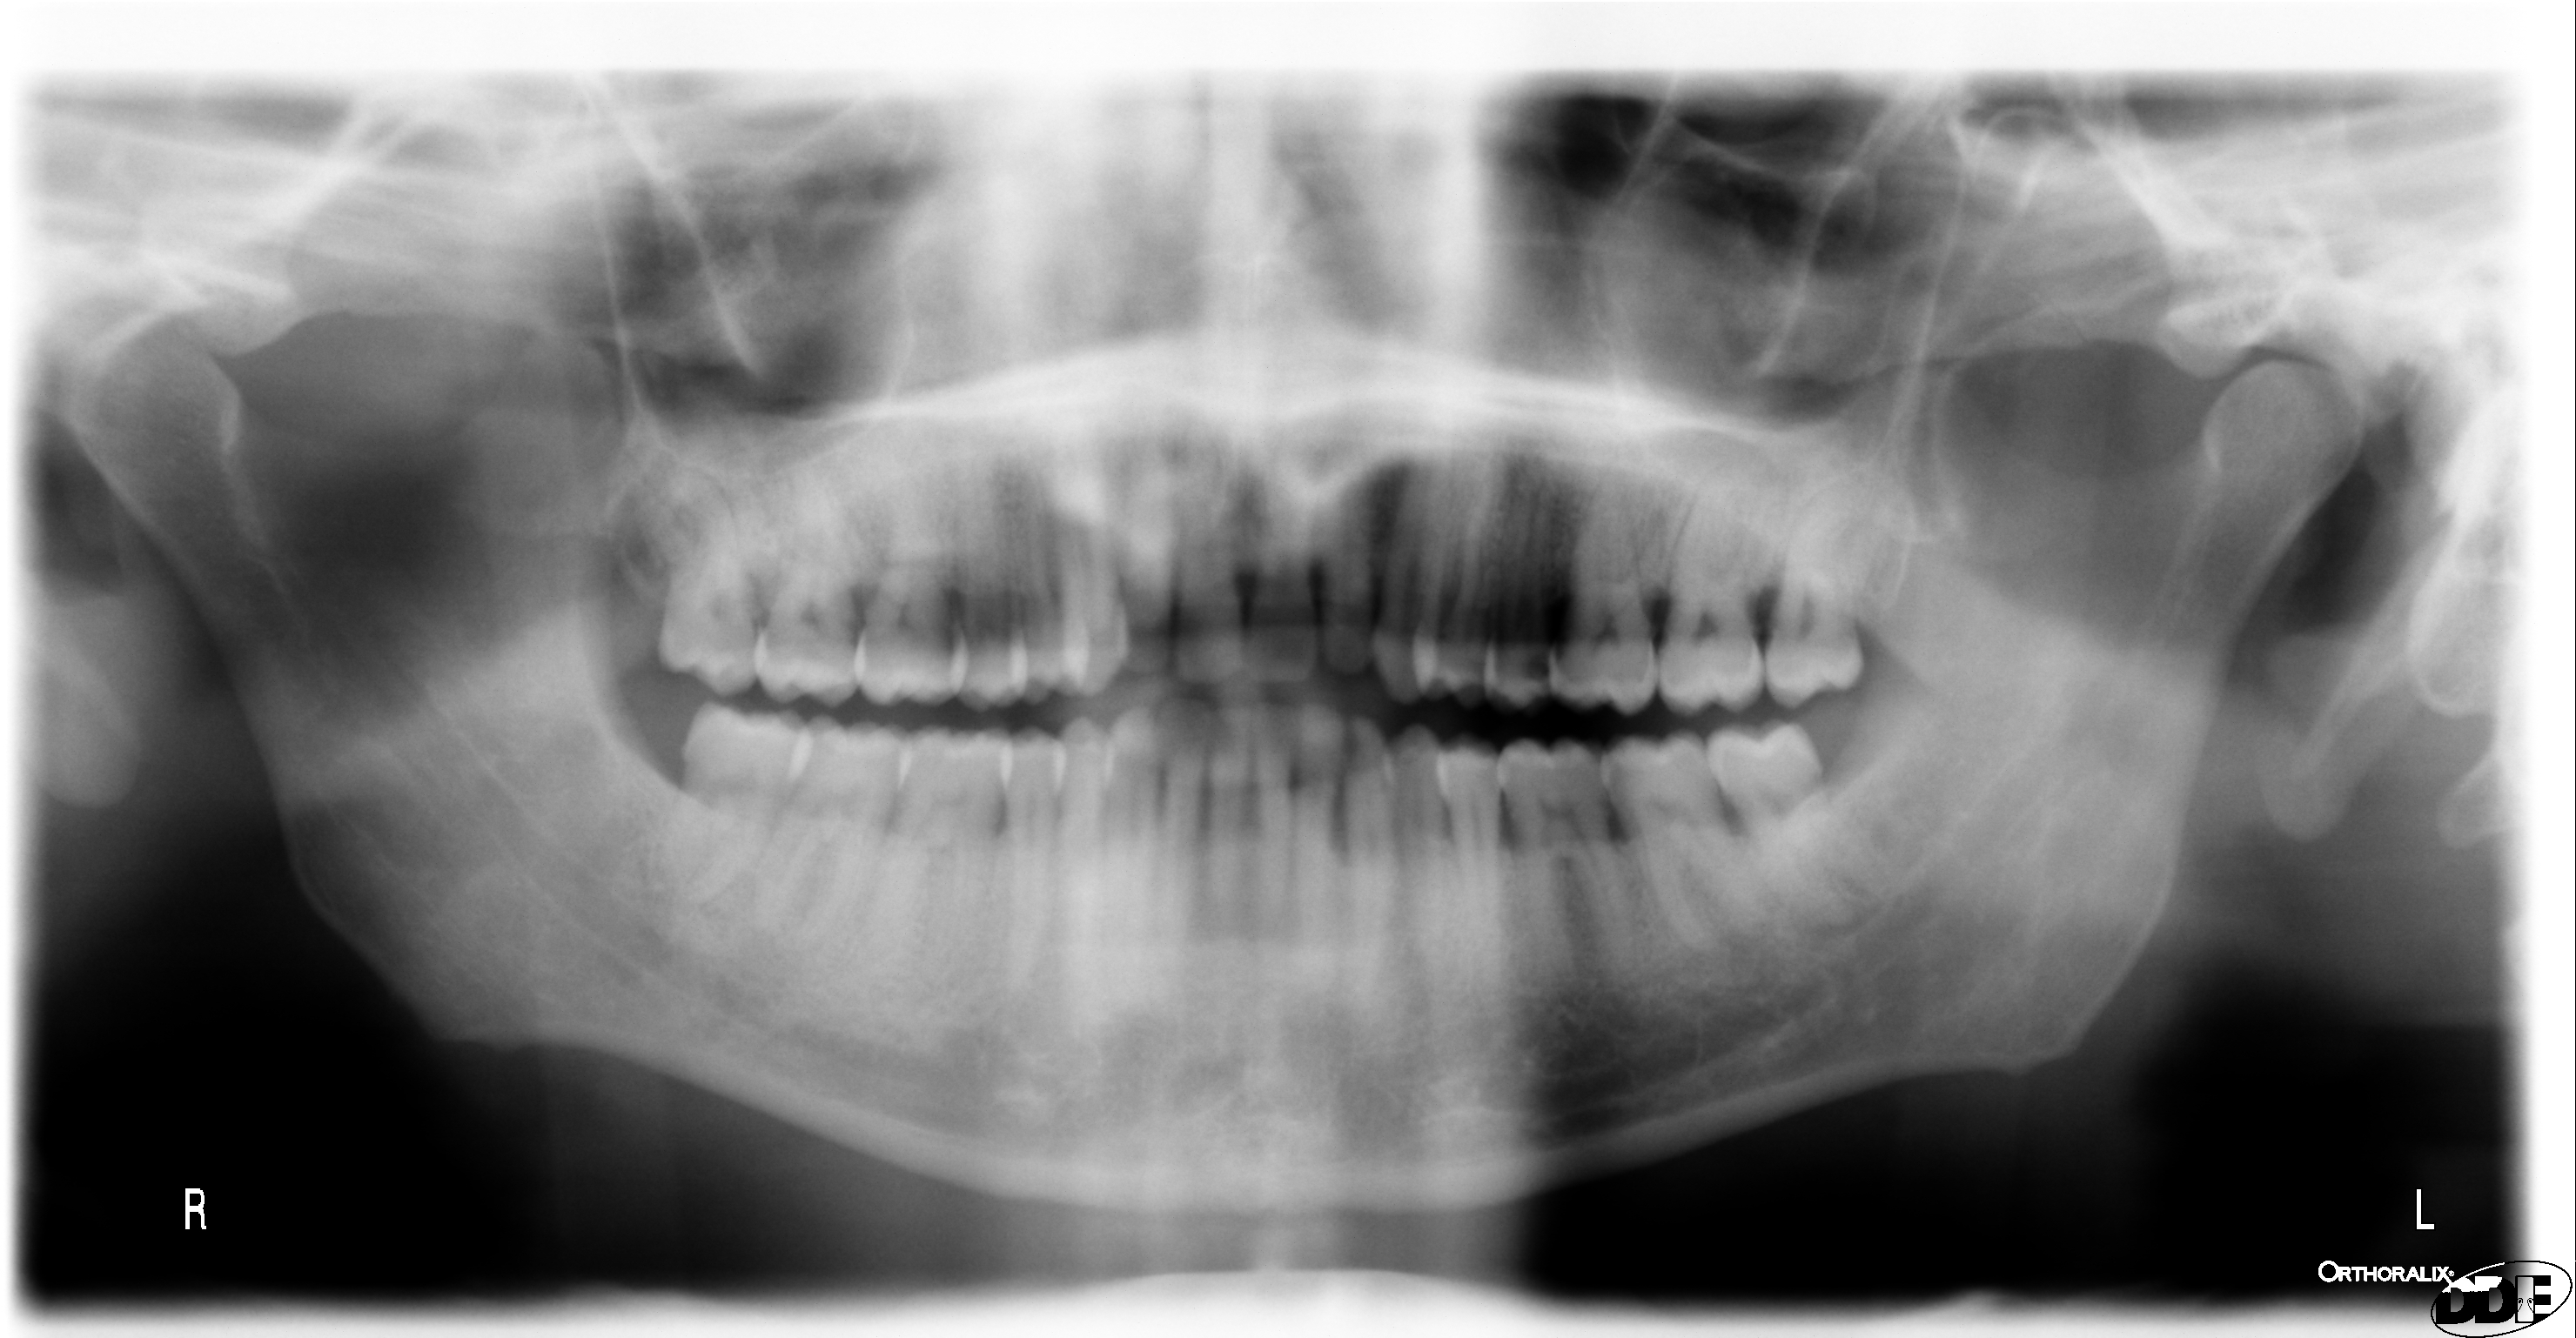

Il dentista può estrarmi un dente del giudizio senza ricorrere a radiografia?

Salve Sono andato a fare la pulizia dei denti e il dentista ha rilevato che il dente del giudizio inferiore è un po' cariato e che potrebbe attaccare la carie al molare davanti. Preciso che il dente del giudizio è uscito quasi del tutto. Vorrei sapere se il dentista può estrarmi tale dente senza ricorrere a radiografia.